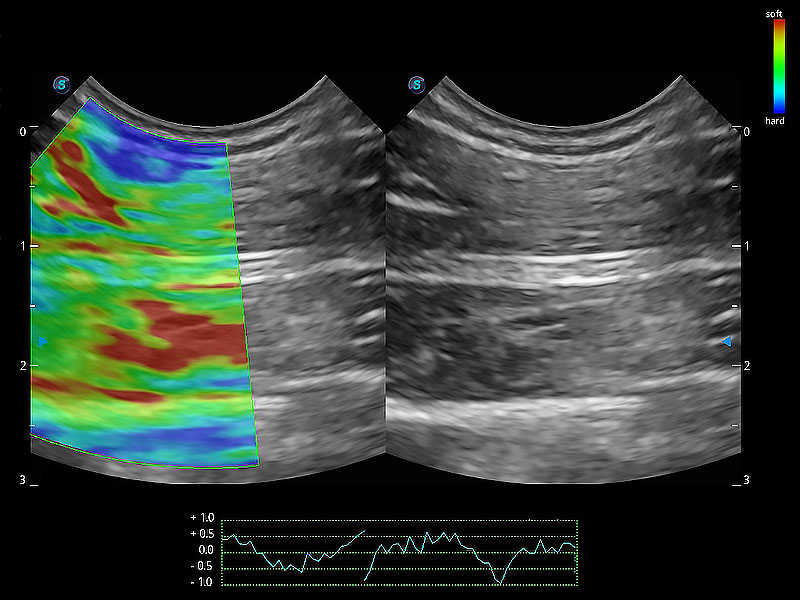

操作简便,无需高频度外力作用即可真实反映组织的形变,快速评估肿瘤良恶性。

实时用颜色表示心肌组织运动,观察和定量组织的运动情況,对快速检测与评估心肌的灌注和活性、电传导及心肌收缩和舒张功能等均能提供重要的诊断信息。